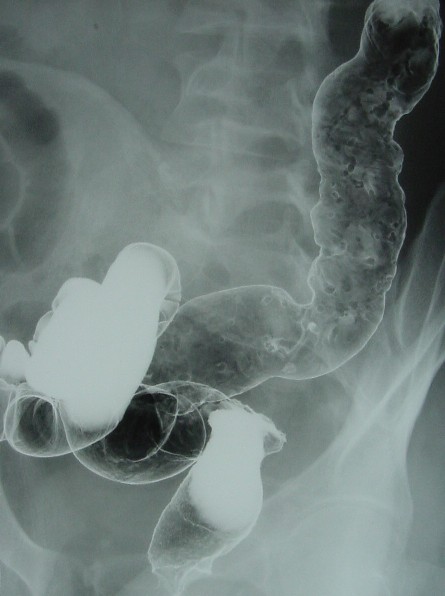

レミ後(2002年12月09日)